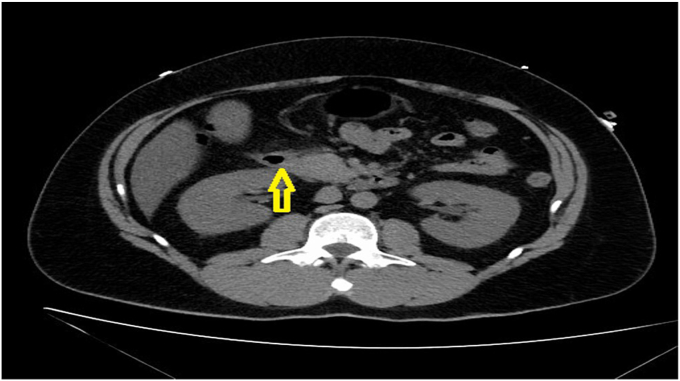

This is a case of 39 year-old male who was diagnosed with acute pancreatitis based on characteristic symptoms and positive CT findings on presentation. Laboratory testing revealed elevated serum glucose 251 mg/dL, low serum bicarbonate 8 mmol/L, increased anion gap 21, and elevated serum beta-hydroxybutyrate 9.62 mmol/L. Diagnosis of DKA was made, however patient did not carry a diagnosis of diabetes mellitus. His hemoglobin A1c in hospital was normal at 5.4%. Additionally, follow-up hemoglobin A1c at 4 months and 10 months postdischarge did not imply diabetes mellitus, 5.8% at both time points. The patient who was initially managed with intravenous insulin required no insulin or oral diabetic medication on discharge. All these findings argued against new onset diabetes mellitus.